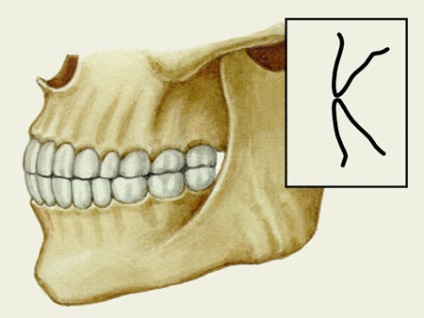

A fő jellemzője, amely megkülönbözteti a közvetlen harapás más fajok jobb befogófogak rejlik a természeténél fogva érintkeznek egymással. Kések nem fedik át egymást a felső állkapocs alsó sor, elzáródás párhuzamosan.

Közvetlen fogazat megfelel a fő jellemzői a helyes elszámolás, hanem azért, mert orthodontists nem mindig javasoljuk, hogy rögzítse. Ugyanakkor úgy véljük, hogy ez a fajta befogófogak negatív következményekkel járhat. Elejét lehet: ezt meg kell, hogy gondosan figyelemmel kíséri a feltétele a száj és a rendszeres fogorvosi látogatások. Nézzük a fotó, akkor láthatjuk, hogy néz ki a záró: a felső fogak nem terjed ki az alsó, van egy full contact az íny területen nincsenek hiányosságok között a metszőfogak.